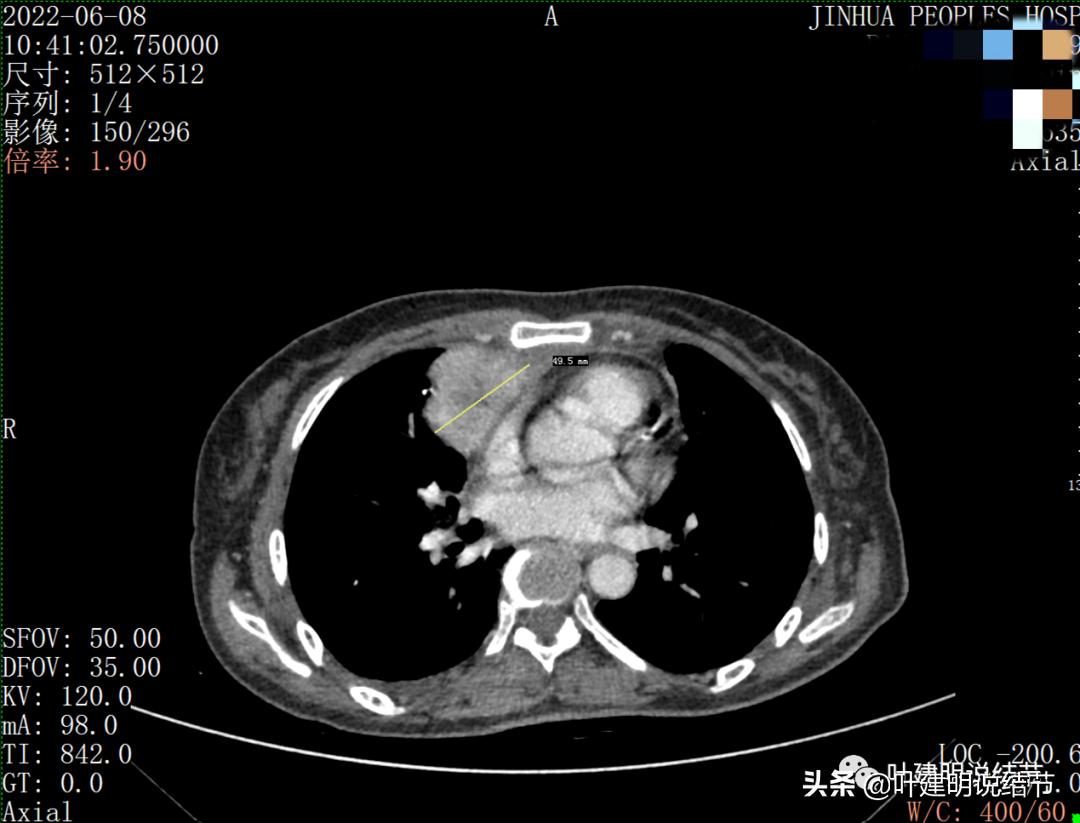

病灶占据前纵隔从上到下全程,多中心,密度不均,对心脏与大血管有压迫,没有明显侵犯

病灶表面不平,中间有坏死

上图示最大横断位达5厘米

纵隔如此巨大的占位,恶性是基本上能肯定的了,到底要考虑淋巴瘤、胸腺瘤、胸腺癌、畸胎瘤或其他恶性肿瘤呢?一般来说,应该是胸腺癌或淋巴瘤可能性为大。再来看看化验检查。